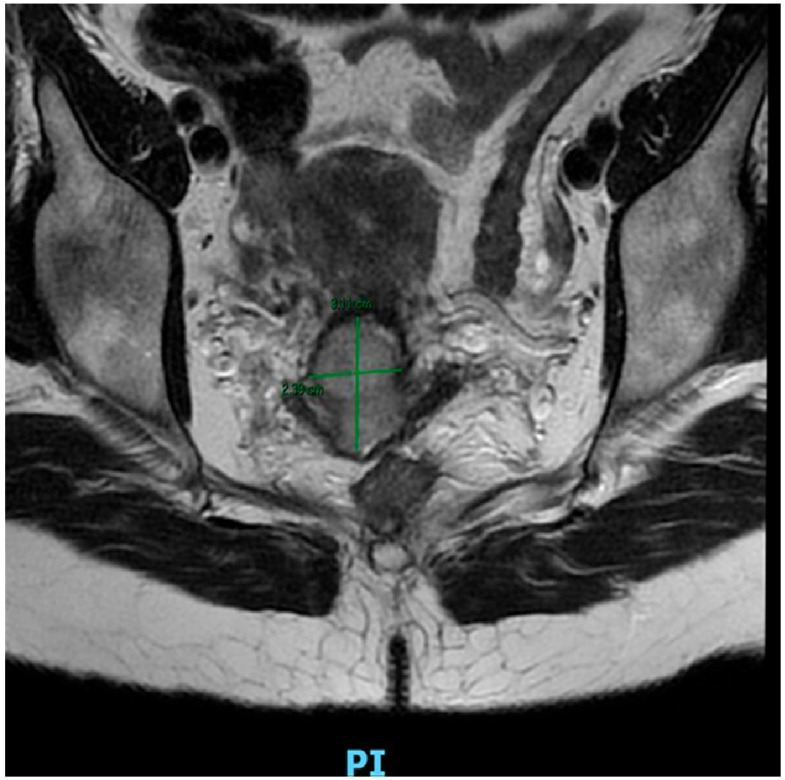

Abstract Image